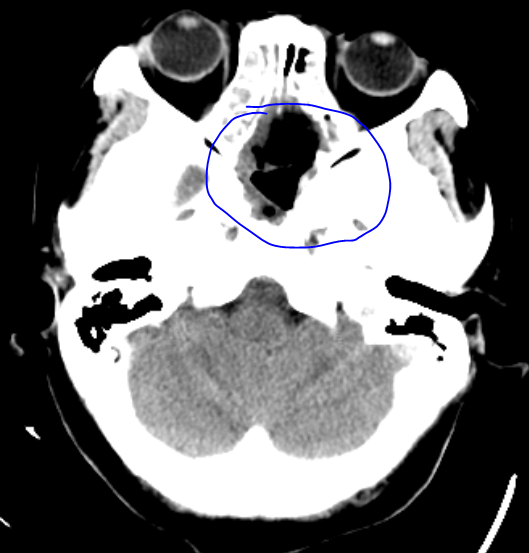

综合意见认为:肿瘤定位明确,有占位效应,见视交叉受压上抬移位,鞍底塌陷,患者目前有视力受损症状,为明确病变性质,解除颅内占位效应,需手术治疗,患者手术指征明确,征得患者及家属同意后,在麻醉科通力合作下为患者施行“神经内镜下经鼻腔-蝶窦垂体除术”,历经2小时10分钟后,手术顺利完成,术后恢复良好,视物不清症状改善,未出现相关术后并发症,患者于术后1周痊愈出院。

术后复查头颅CT见肿瘤全切